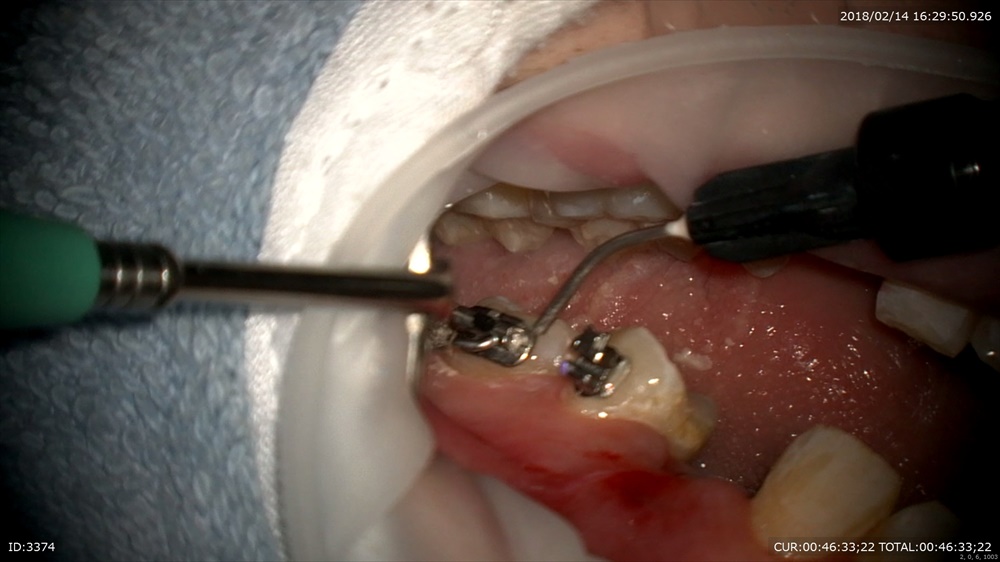

装置装着 デーモンシステム。師事している武内先生が第一人者のシステム。本当に矯正期間が短い。弱い力で動くので痛くない。私は色々なシステムをこれまで使用しましたが歯周組織にも優しいのは私の臨床に大切です。

マイクロスコープで正確に。

六番、七番間にミニスクリュー。

無痛。